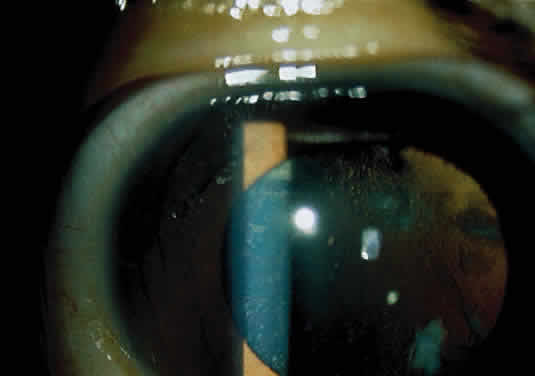

Corneal clouding (Fig. 10), hyperopic astigmatism, and a mild retinopathy with surface-wrinkling maculopathy (Fig. 11) appear to be the constant ocular triad.75 Some patients have retinal vascular tortuosity, optic nerve head swelling (Fig. 12), visual field defects, and abnormalities in color vision. Visual complaints are uncommon.

Fig. 10. Mild corneal clouding in a child with mucolipidosis III. (Traboulsi E, Maumenee I: Ophthalmologic findings in mucolipidosis III. Am J Ophthalmol 102:529, 1986)

Fig. 11. Surface-wrinkling maculopathy in a patient with mucolipidosis III. (Traboulsi E, Maumenee I: Ophthalmologic findings in mucolipidosis III. Am J Ophthalmol 102:529, 1986)

Fig. 12. Optic nerve head swelling in a patient with mucolipidosis III. (Traboulsi E, Maumenee I: Ophthalmologic findings in mucolipidosis III. Am J Ophthalmol 102:529, 1986)